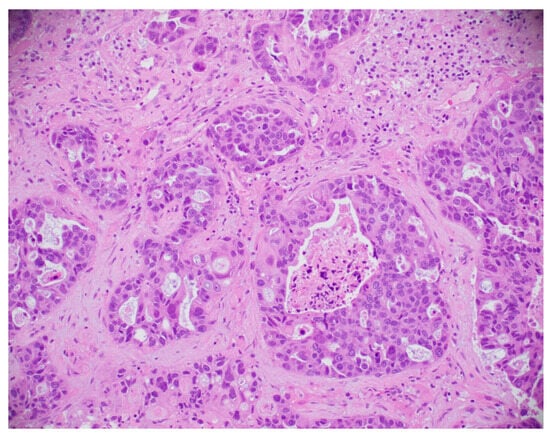

8.5. Histopathological Image-Based Breast Cancer Detection

8.5.1. Model Performance on Histopathological Image: Pros, Cons, and Future Directions